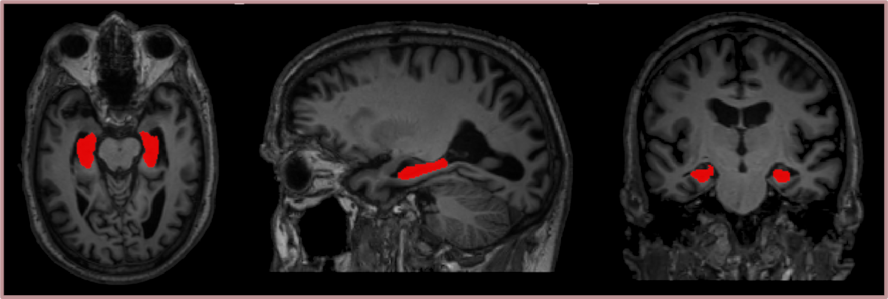

Our following works have instead been focusing on the development of image processing tools that can be employed to identify and analyse neurodegenerative patterns in the brains of dementia patients, with a special focus on Alzheimer’s patients. Our methods are being tested in several large databases, available at the Geriatrics unit of Karolinska university hospital Huddinge and containing image data, from patients with several types of dementia as well as from normal controls. In particular, we developed an automatic hippocampal segmentation tool that integrates a statistical shape model of the hippocampus into a traditional deep learning-based segmentation pipeline. This method achieves a high accuracy not only on healthy controls, but also on Alzheimer’s patients where automatic segmentation is usually more challenging due to their hippocampal atrophy. Moreover, we are currently working on the creation of a deep learning-based tool for brain segmentation quality control.

• I. Brusini et al., "Shape Information Improves the Cross-Cohort Performance of Deep Learning-Based Segmentation of the Hippocampus," Frontiers in Neuroscience, vol. 14, 2020.